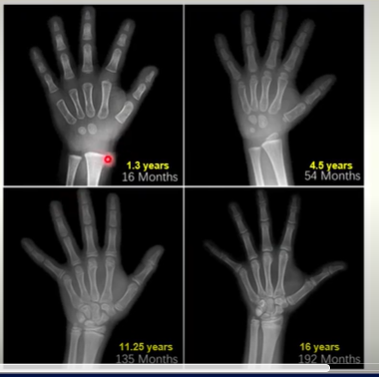

Growing bone example (mouse)

Hand X-rays

Bone Growth

Length (interstitial growth)

bones grow in length via endochondral ossification at the growth plate

actively proliferating plate of cartilage

converted to trabecular bone

progressively increases length of the bone

becomes epiphyseal line (after it ossifies)